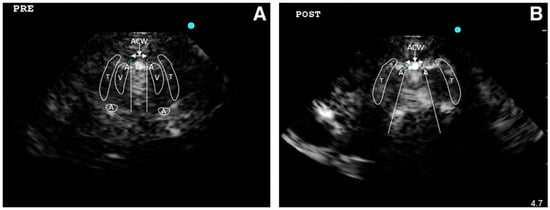

4.1.1. Endotracheal Tube (ETT) Positioning Assessment

4.1.2. Upper Airways Damage Identification and Procedures